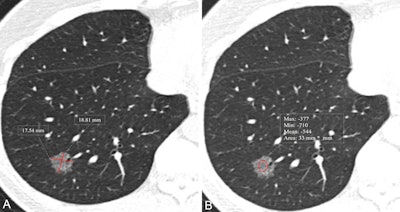

CT images show measurement of nodule size and mean CT attenuation in a 52-year-old woman. Transverse lung-window CT images were obtained without administration of contrast material. This lesion was pathologically proven to be an invasive adenocarcinoma. (A) Nodule size was measured by taking the mean of the maximum length and maximum width, defined as perpendicular to the length on the same axial image showing the maximum area of the nodule. The red lines indicate the length and width and measure 17.5 mm and 18.8 mm, respectively. (B) Nodule CT attenuation was measured by placing three regions of interest within the nodule covering two-thirds of the largest area while avoiding vessels and bronchioles. The red circle indicates CT attenuation and measures -544 HU.RSNA